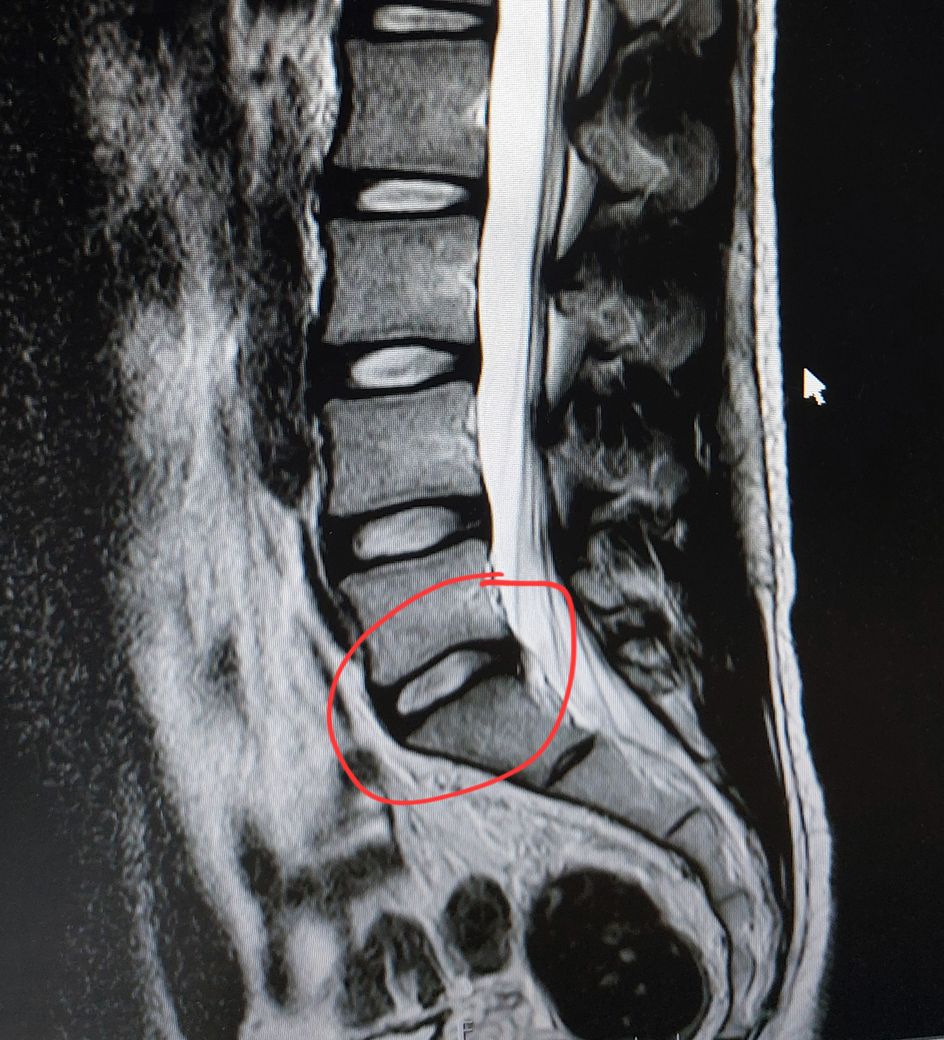

• 3번 째 사진

멸개월전부터 요추가 뻣뻣하고 시큰거리다가 최근에 좀 나아지긴 해도 만성적이라서 오늘 mri 찍고 허리디스크 진단받았습니다

(요추 맨 밑 천추 위 디스크)

신경이 심하게 눌리고 있지는 않은 것으로 보입니다. 충분히 휴식하여 주시고, 허리에 무리가 많이가는 자세는 당분간은 피해주시는 것이 좋습니다.